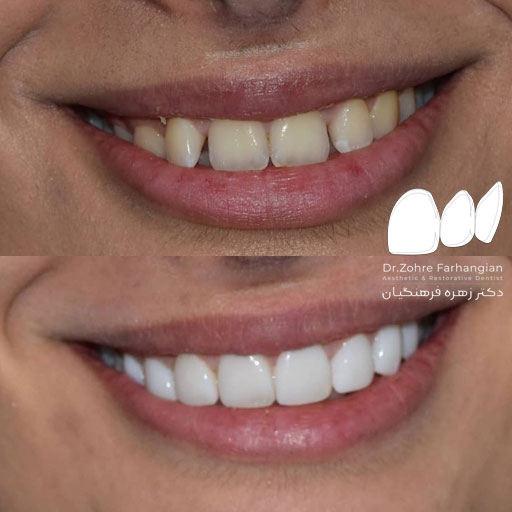

نمونه کار شماره ۲۰ کامپوزیت ونیر

۷ واحد ونیر کامپوزیت با رنگ طبیعی برای فک بالا

مراحل درمان به شرح زیر:

۱.ریموو کردن کامپوزیت ونیر چهاردندان قدامی (به علت ناراضی بودنشون از آناتومی دندونها)

۲.انجام ۷واحد ونیر کامپوزیت با رنگ طبیعی

۳.و یک واحد رزین بانددبریج برای دندان پره مولر اول سمت چپ بصورت موقت (که در آینده ایمپلنت خواهد شد.)

طراحی لبخند زیبا 😍